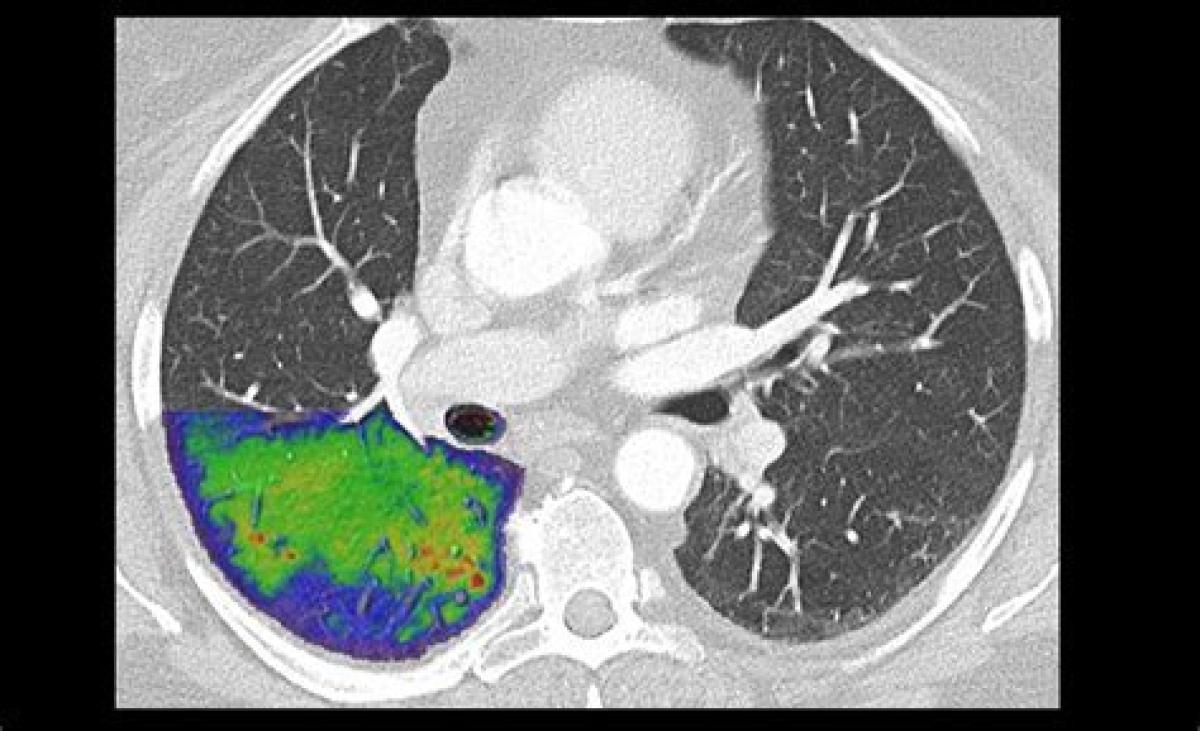

توموگرافی کامپیوتری شمارش فوتون (PCCT) شکلی از توموگرافی کامپیوتری اشعه ایکس (CT) است که در آن اشعه ایکس با استفاده از آشکارساز شمارش فوتون (PCD) که برهمکنش‌های فوتون‌های منفرد را ثبت می‌کند، شناسایی می‌شود. با پیگیری انرژی ذخیره‌شده در هر تعامل، پیکسل‌های آشکارساز PCD هر کدام یک طیف انرژی تقریبی را ثبت می‌کنند و آن را به یک تکنیک CT طیفی یا انرژی تفکیک‌شده تبدیل می‌کنند. در مقابل، اسکنرهای متعارف سی تی از آشکارسازهای ادغام کننده انرژی (EID) استفاده می کنند، که در آن انرژی کل (به طور کلی از تعداد زیادی فوتون و همچنین نویز الکترونیکی) که در یک پیکسل در طول یک دوره زمانی ثابت ذخیره می شود، ثبت می شود. بنابراین، این EID ها فقط شدت فوتون را ثبت می کنند که با عکاسی سیاه و سفید قابل مقایسه است، در حالی که PCD ها نیز اطلاعات طیفی را ثبت می کنند، مشابه عکاسی رنگی.